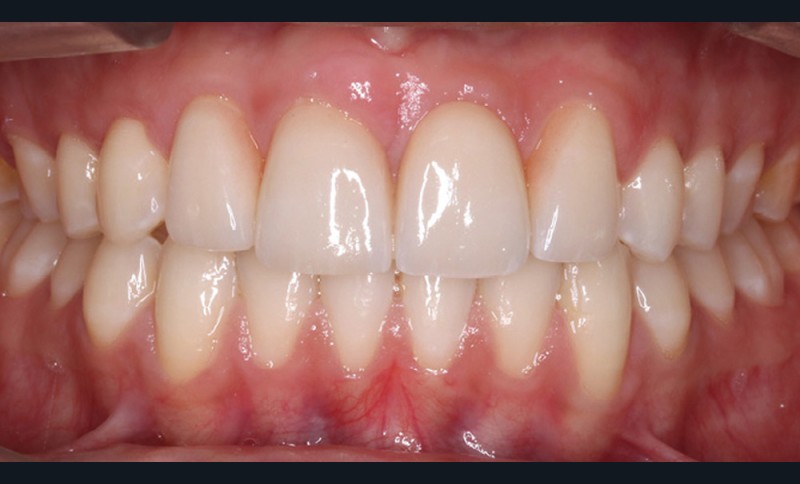

Antony, 11 ans se présente initialement pour une demande esthétique concernant ses deux incisives centrales qu’il trouve trop grosses (fig. 1a-c).

Le profil est convexe et associé à une inocclusion labiale au repos. Il s’agit d’une classe II squelettique sur un schéma facial normodivergent. Les rapports occlusaux sont de classe II bilatérale (complète au niveau molaire) avec des incisives inférieures vestibulo-versées. La 21 est géminée et la 11 vraisemblablement fusionnée avec un germe surnuméraire, sans altération de la formule dentaire. Du fait du diamètre mésiodistal fortement augmenté des incisives centrales, et du manque de place à l’arcade maxillaire qui en découle, les 12 et 22 sont en inversé d’occlusion en palato position. Les 53 et 63 sont persistantes sur l’arcade avec une inclusion en transposition incomplète de la 13, dont la cuspide se situe entre la racine de la 12 et celle de la 11 résorbée (fig. 1d-g).